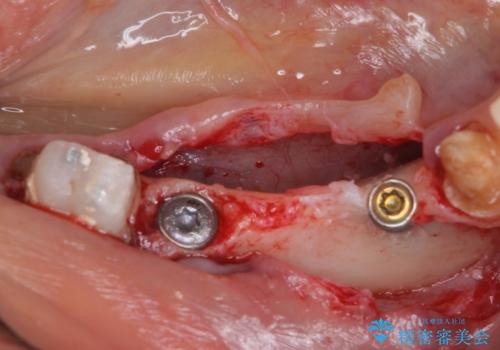

下顎右側は骨造成を併用してインプラント治療を行い、その他の奥歯もインプラントや歯周外科処置を併用して補綴治療を進め、最後に前歯部の欠けてしまったセラミッククラウンを作り替えることとしました。

- 外科手術のため、術後に痛みや腫れ、違和感を伴います

- メンテナンスを怠ったり喫煙により、お口の中に大きな悪影響を及ぼすインプラント周囲炎等にかかる可能性があります

- 外科手術のため、術後に出血、痛みや腫れ、違和感を伴います